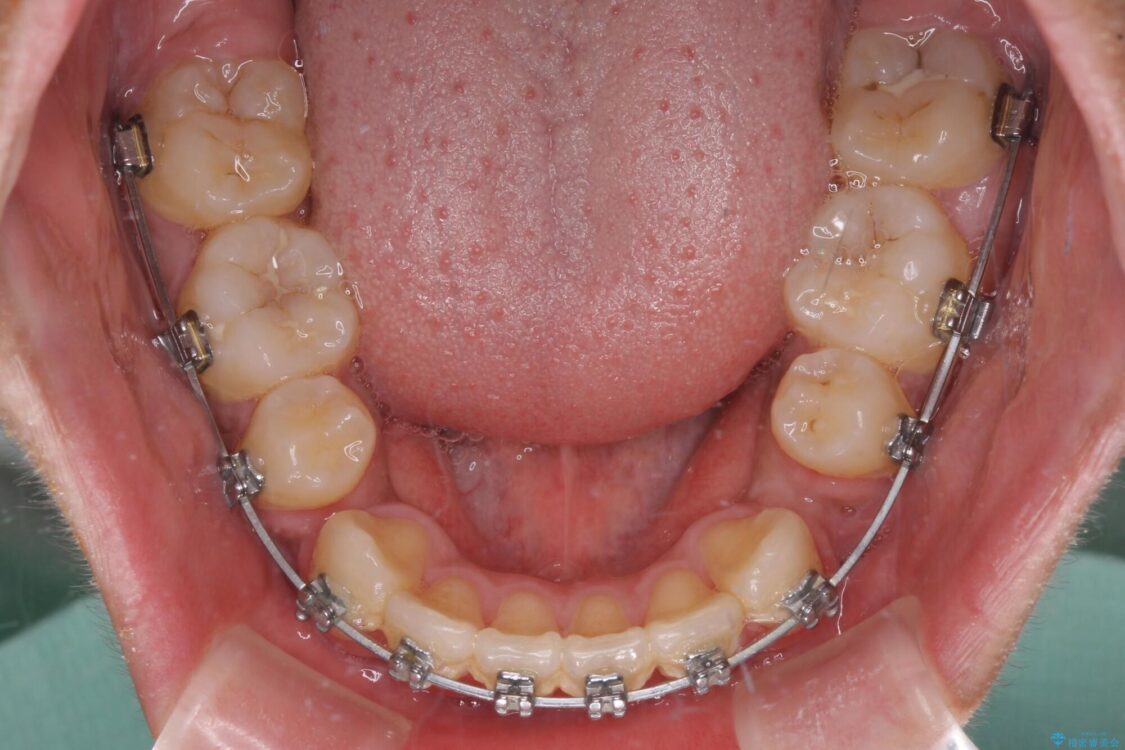

治療途中

• 膨らんだ口元 ワイヤー装置での抜歯矯正 治療途中画像